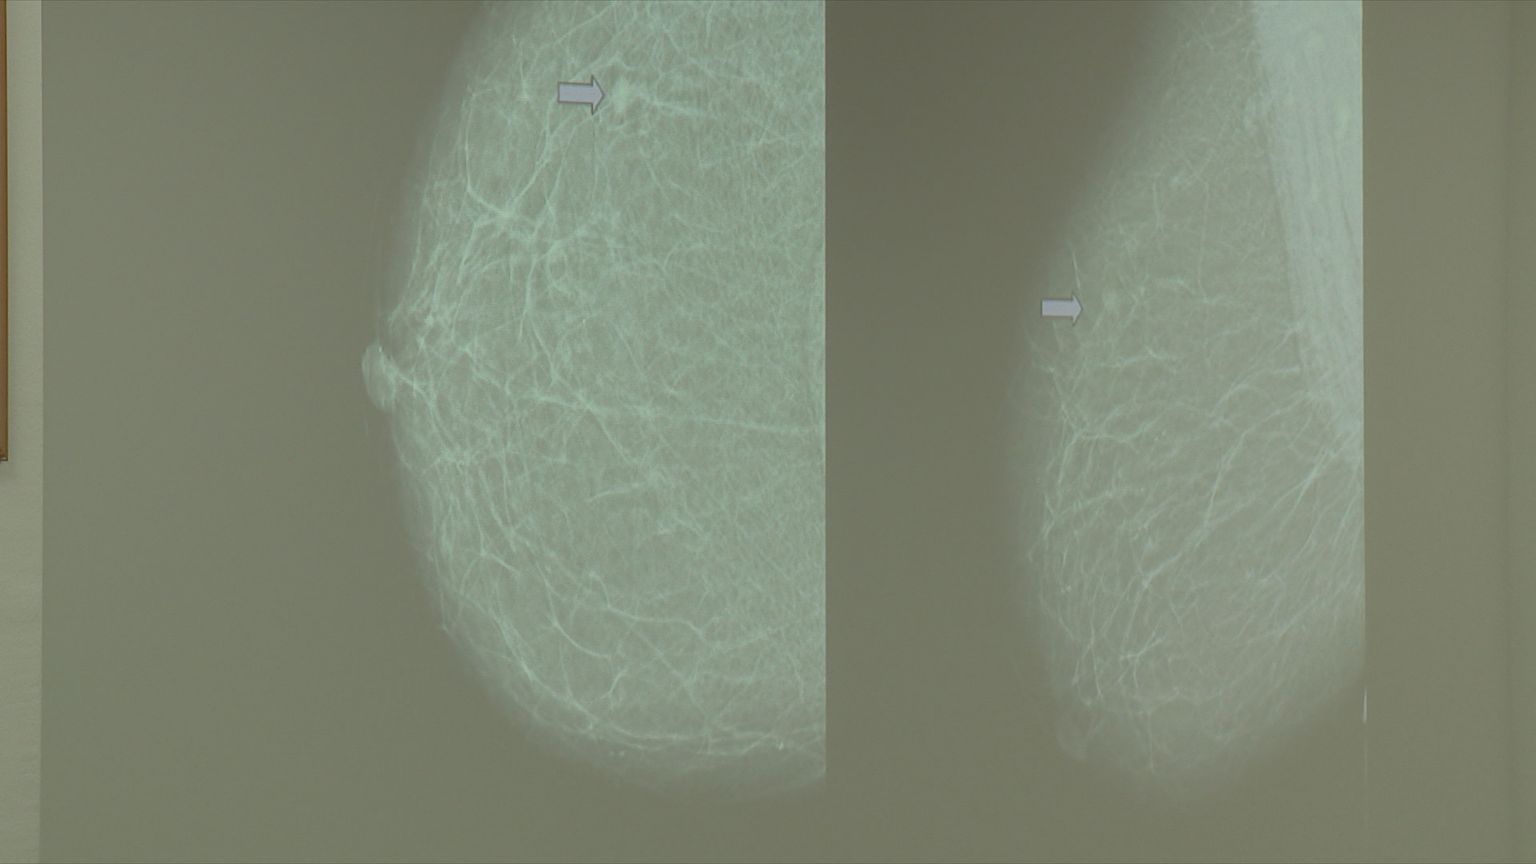

• Rak dojke, ilustracija - 4 Foto: DNEVNIK.hr

• Rak dojke, ilustracija - 3 Foto: DNEVNIK.hr

• Rak dojke, ilustracija - 2 Foto: DNEVNIK.hr

• Rak dojke, ilustracija - 1 Foto: DNEVNIK.hr